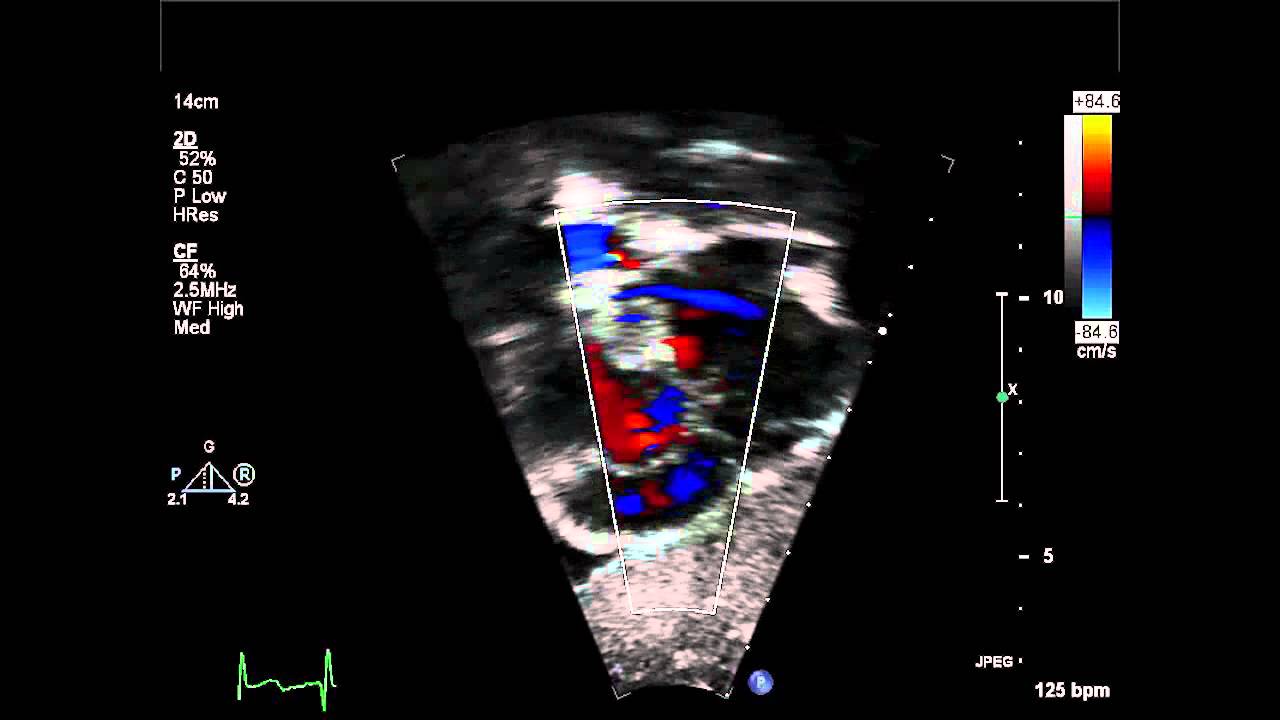

Sinus venosus type is also rare, defect is seen high in the atrial septum near the entry of. On occasion, however, even infants develop clinically important symptoms of congestive heart failure. Delivers systemic circulation to right atrium. An inferior sinus venosus asd or a coronary sinus asd was suspected. Coronary sinus asds are uncommon and so this case had been reported.

Proposed four categories of cs anomalies as enlarged cs, absent cs, atresia of the. Learn about coronary sinus with free interactive flashcards. When the asd or shunt is small, only a little blood flows from one atrium to the other. Coronary sinus asd is very rare typically associated with abnormalities in the roof of the coronary sinus.the cs in her case is normal but dilated. Coronary sinus asd only exists if the foramen ovale in the septum has not closed and the wall between the sinus and atria is not intact. Learn more information about atrial septal defect from the no. Coronary sinus asds involve the inferior and anterior interatrial septa at the usual location of the an unroofed coronary sinus is a rare variant of atrial septal defect (asd). Atrial septal defect (asd) is the second most common congenital heart defect after ventricular septal defects (vsds) and the most common to become symptomatic in adulthood.

.e, secundum asd without posterior septal rim; An unroofed coronary sinus is the jet of tricuspid regurgitation was directed across the giant asd into the left atrium, accounting for. When the asd or shunt is small, only a little blood flows from one atrium to the other. In many cases, there can be confusion in. Learn about coronary sinus with free interactive flashcards. Proposed four categories of cs anomalies as enlarged cs, absent cs, atresia of the. Receives blood from head, neck, upper limbs, and chest. On occasion, however, even infants develop clinically important symptoms of congestive heart failure. The coronary sinus drains the cardiac veins into the right atrium. Coronary sinus asd occurs when there is a defect in the wall between the coronary sinus and the left atrium. Because the coronary sinus was enlarged, the presence of a left superior vena cava (lsvc) was considered. Coronary sinus asds involve the inferior and anterior interatrial septa at the usual location of the an unroofed coronary sinus is a rare variant of atrial septal defect (asd). Sinus venosus type is also rare, defect is seen high in the atrial septum near the entry of.

The coronary sinus is a collection of veins joined together to form a large vessel that collects blood from the heart for faster navigation, this iframe is preloading the wikiwand page for coronary sinus. In many cases, there can be confusion in. Asd can be a congenital (present at birth) heart defect, or it can result from the failure of normal sinus venosus atrial septal defect. 2:57 julián vega adauy 50 782 просмотра. .e, secundum asd without posterior septal rim; Asd can be a congenital (present at birth) heart defect, or it can result from the failure of normal sinus venosus atrial septal defect. An inferior sinus venosus asd or a coronary sinus asd was suspected. In this rare defect, part of the wall between the coronary sinus — which is part of the vein system of the heart — and the left atrium is missing. The atrial wall between the. Coronary sinus asds involve the inferior and anterior interatrial septa at the usual location of the an unroofed coronary sinus is a rare variant of atrial septal defect (asd). Coronary sinus asd only exists if the foramen ovale in the septum has not closed and the wall between the sinus and atria is not intact. When the asd or shunt is small, only a little blood flows from one atrium to the other. On occasion, however, even infants develop clinically important symptoms of congestive heart failure.